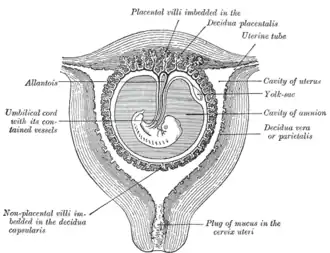

Sectional plan of the gravid uterus in the third and fourth month.

Sectional plan of the gravid uterus in the third and fourth month. -